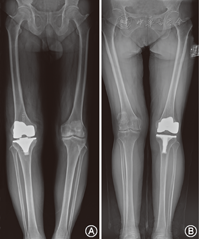

随访期间所有患者术后X线评估,假体位置、对线良好,未见松动、移位等(图1)。国产组和对照组假体术后机械轴偏差值分别为-3.4°±2.5°和-3.0°±2.7°,差异亦无统计学意义(t=-0.408,P=0.685)。